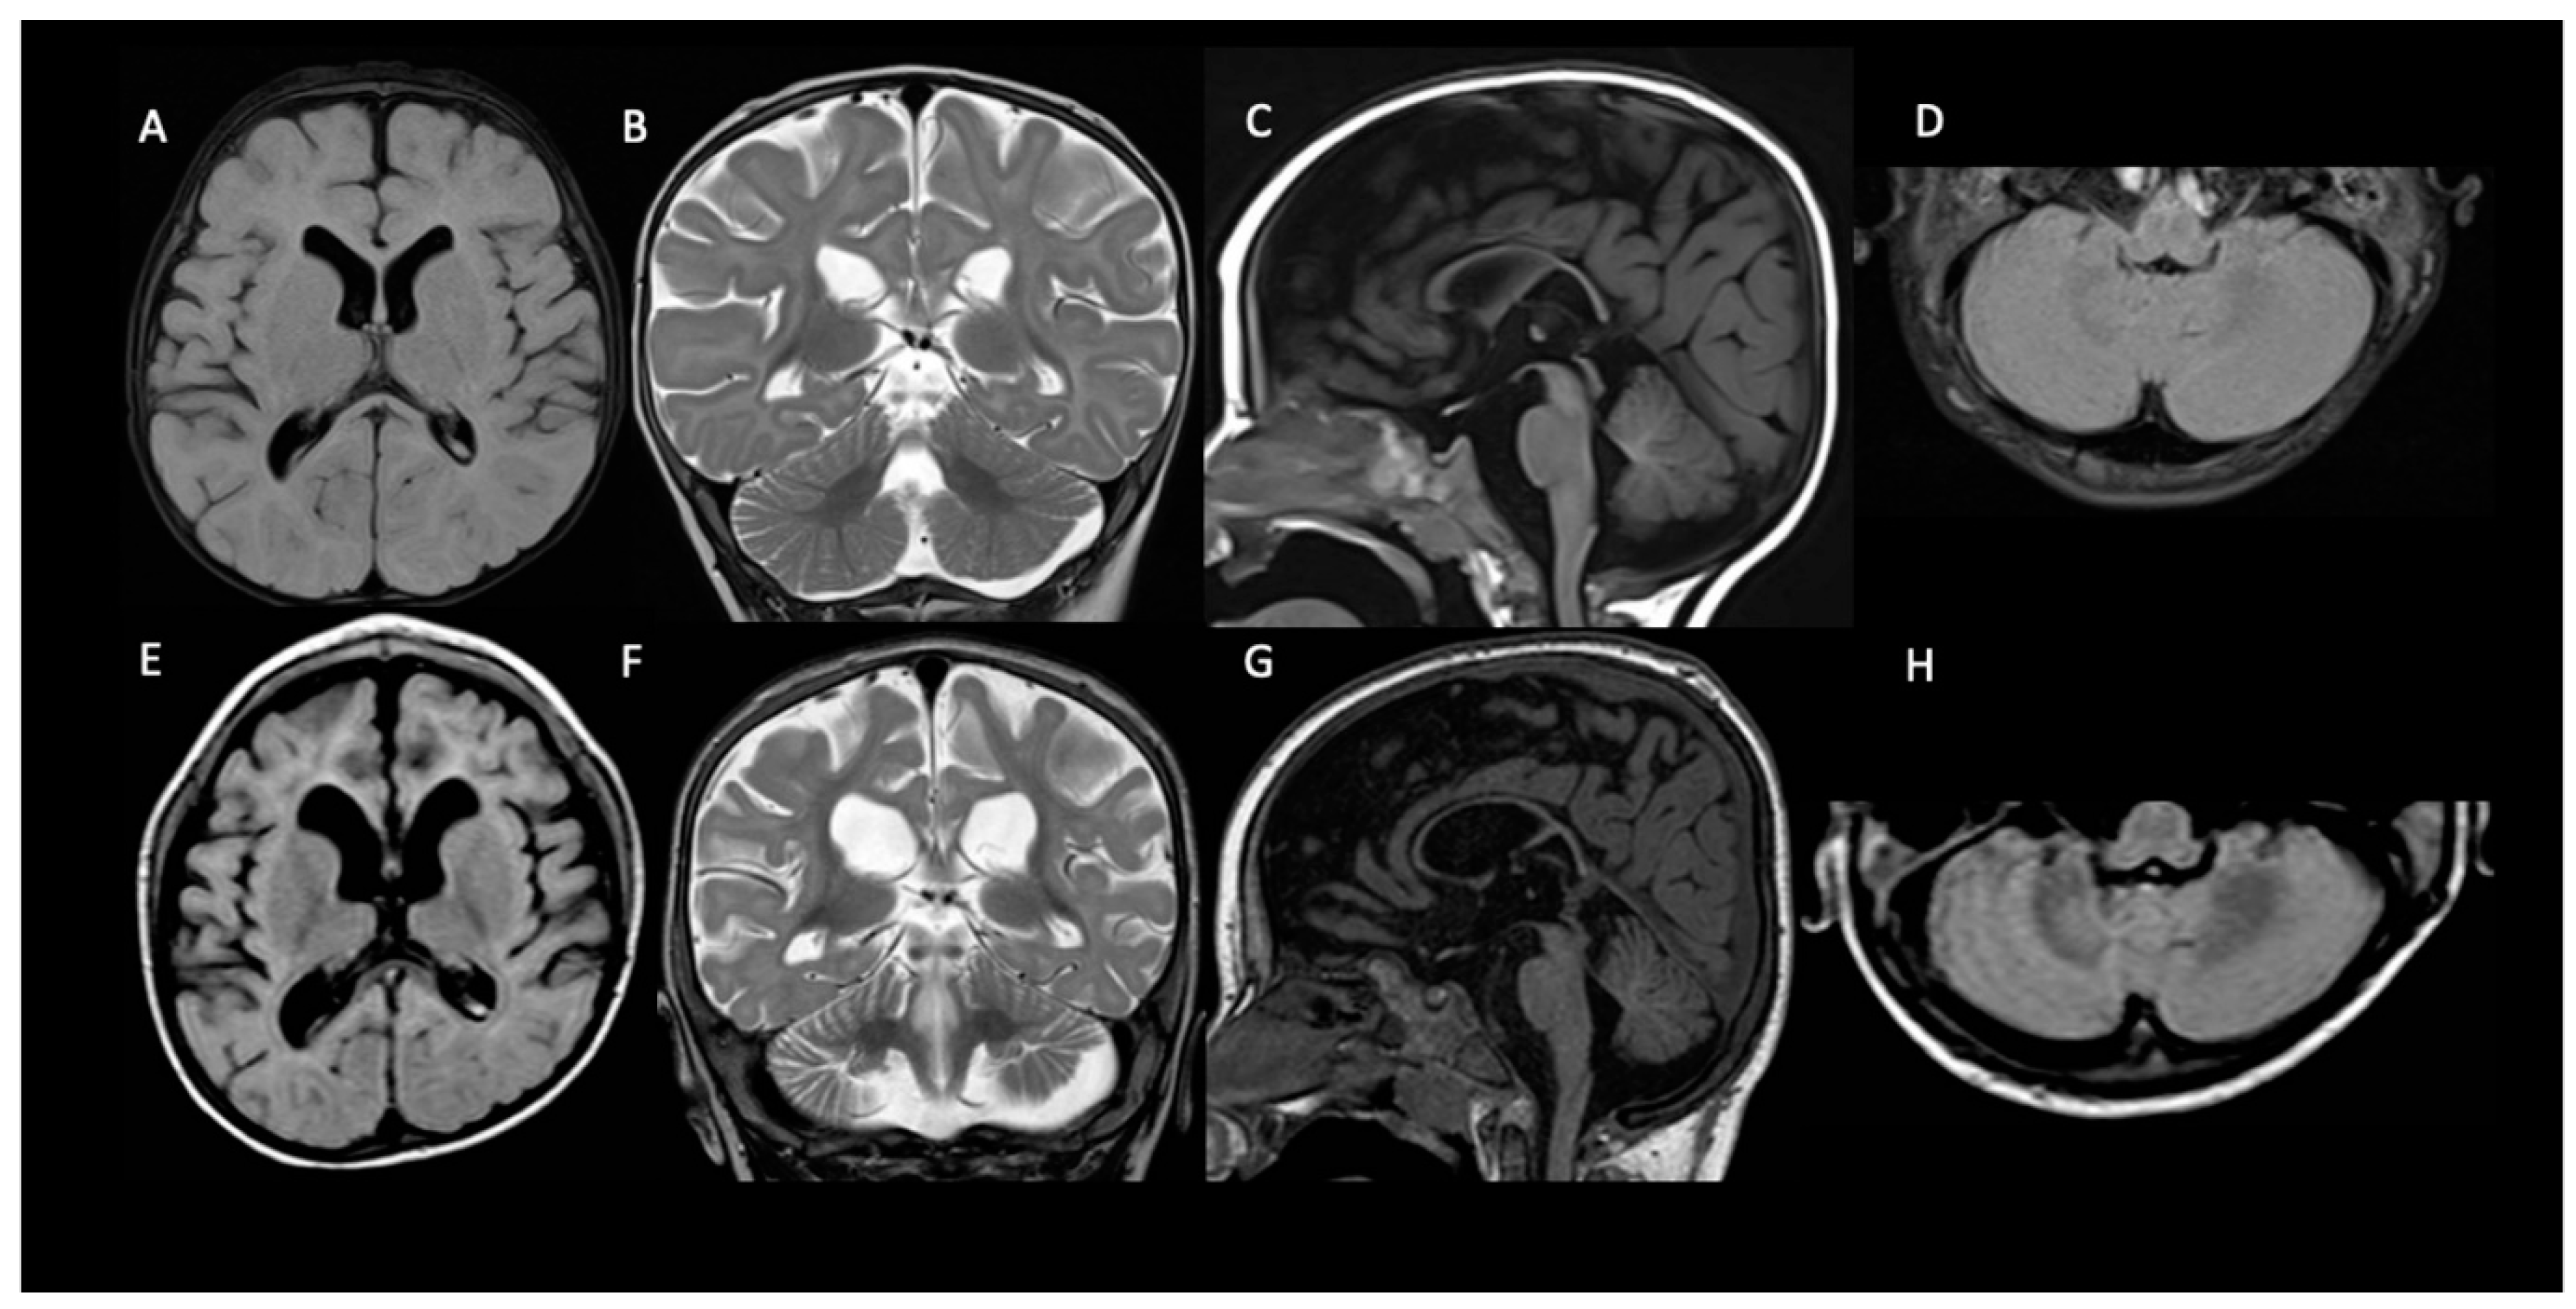

At the QND dose of 15 mg/kg/day, a slight prolongation of QTc interval (470 msec) in the ECG was seen, and the dose was reduced to 12 mg/kg/day until QTc normalization. Concomitant ASMs were unchanged. Dose reduction resulted in a QND plasma concentration of 0.073 μg/mL. Normalization of QT allowed us to slowly increase the QND dose from 12 up to the current dose of 40 mg/kg/day. At the same time, we started to also monitor H-QND levels. Upon reaching the current QND dose, seizure frequency decreased by approximately 90% (less than 3–5 episodes per day). A QND dose of 17.5 mg/kg/day led to a QND and H-QND plasma concentration of 0.096 and 0.045 μg/mL, respectively. At the last follow-up visit, this patient was receiving 40 mg/kg/day of QND resulting in plasma levels of 0.80 and 0.073 μg/mL for QND and H-QND, respectively. EEG performed at the age of 5.5 years showed slowing of the background activity with bitemporal spikes and an absence of physiological sleep figures. During the follow-up, interictal epileptiform abnormalities decreased, but no improvement in the background was seen. The brain MRI at 6 months of age was reported as normal except for a thickness of corpus callosum; a second brain MRI at the age of 2.5 years showed progressive supratentorial and cerebellar atrophy (Figure 2). At the last follow-up (5 years and 9 months of age), cognitive and motor development was severely delayed; neurological examination revealed hand apraxia, poor eye contact with minimal response to social interactions, and severe hypotonia: these symptoms minimally improved with QND.

Neuroimaging has not been analyzed systematically in KCNT1-related DEE, although scattered case reports have documented either normal brain anatomy or—less often—cortical atrophy and thin corpus callosum [20,21]. In our three patients, the brain MRI performed at the epilepsy onset was normal, and in patient 1, in whom the neuro-imaging was repeated at 2.5 years, there was cerebral and cerebellar atrophy with a thinning of the corpus callosum.

Figure 2. Progressive brain atrophy in patient 1. Compared to brain MRI performed at 6 months of age (AD), MRI performed at 2.5 years of age (EH) show progressive ventricular and CSF enlargement (E,F) more prominent in the frontal-temporal regions (E) and a widening of the interfolial cerebellar spaces of both cerebellar hemispheres (G,H) with a further thinning of the corpus callosum (G).